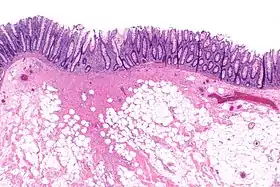

![]() Micrograph showing a colorectal polypectomy scar. H&E stain. | |